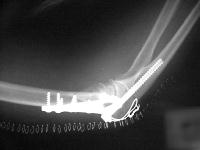

the operating surgeon decided to achieve stability with triple tension band fixation and bone graft:

Click for larger image

A triangle of tension bands was constructed using 1.6 and 2.0 mm pins, with the most distal pin transfixing all four distal fracture fragments. It would have been possible to add a wire through the center of the cannulated screw for an additional cerclage proximally, but this was not done because of concerns regarding corrosion at the titanium/stainless contact point. Although one pin appears to be within the old cannulated screw, it is not.